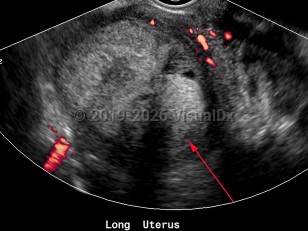

Imaging Studies image of Endometrial carcinoma - imageId=6841123. Click to open in gallery.  caption: '<span>Sagittal color Doppler image of uterus with complex mass, with no internal vascularity, pathology-proven endometrial sarcoma.<br /></span>'

Sagittal color Doppler image of uterus with complex mass, with no internal vascularity, pathology-proven endometrial sarcoma.